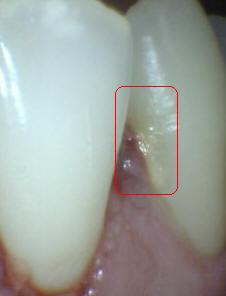

Sistema Internacional para la Detección y Evaluación de Caries (ICDAS)

¿Determine los códigos pertinentes a cada imagen?

Click en el hipervínculo: Para comparar el resultado de su diagnóstico